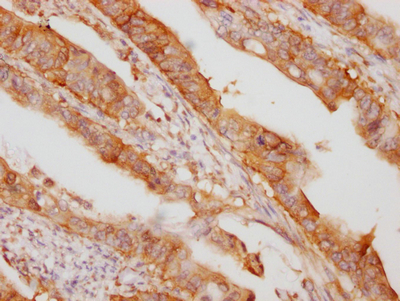

CSB-RA932542A0HU

IHC image of CSB-RA932542A0HU diluted at 1:100 and staining in paraffin-embedded human colon cancer performed on a Leica BondTM system. After dewaxing and hydration, antigen retrieval was mediated by high pressure in a citrate buffer (pH 6.0). Section was blocked with 10% normal goat serum 30min at RT. Then primary antibody (1% BSA) was incubated at 4℃ overnight. The primary is detected by a Goat anti-rabbit IgG polymer labeled by HRP and visualized using 0.05% DAB.